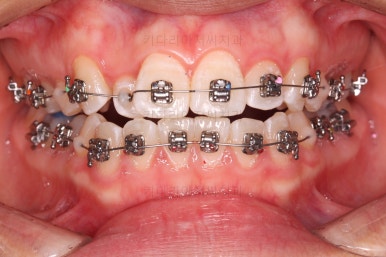

이번 환자분이 선택하신 장치는 엠파워 메탈이라고 하는 자가결찰 금속장치에요.

철사를 잡아주는(결찰) 뚜껑이 장치에 달려있는 (자가)장치이며, 재질이 금속인 장치에요.

금속 장치는 가장 튼튼하고 부피도 작고 비용도 저렴하다는 장점이 많은 장치입니다.

장치 부착 직후의 느낌을 참고해 주세요.

적절한 시기에 발치를 하고요.

앞니의 덧니 느낌은 벌써 많이 좋아졌네요.